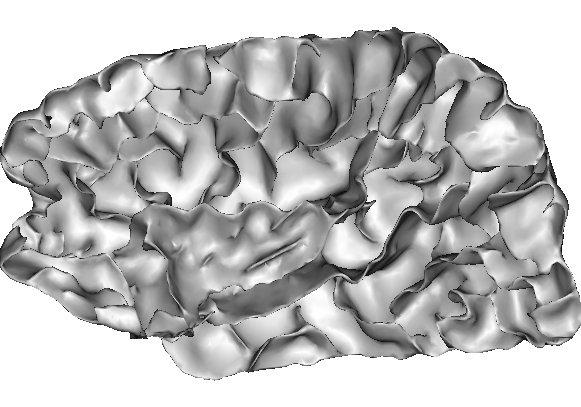

4. Last step, the detection of the putative burried gyri. The goal is to add into the cortex folding representation the necessary information to study the sulcal root notion. We are aiming indeed at defining a model of the cortical folding patterns built upon indivisible elementary units that may correspond to the first folds appearing during in utero life. This research program wants to overcome the weaknesses of the usual descriptions of the sulcus interruptions, a phenomenon which can even occur for the central sulcus:

We try to split the central sulcus at the level of the middle "pli de passage", which defines the two underlying sulcal roots. Viewed from beneath:

The simple surfaces are split into several pieces when depth variations or high values of the Gaussian curvature are clues of some putative gyrus. The current procedure is still far to be fully satisfying. Current efforts to improve it may be found in: